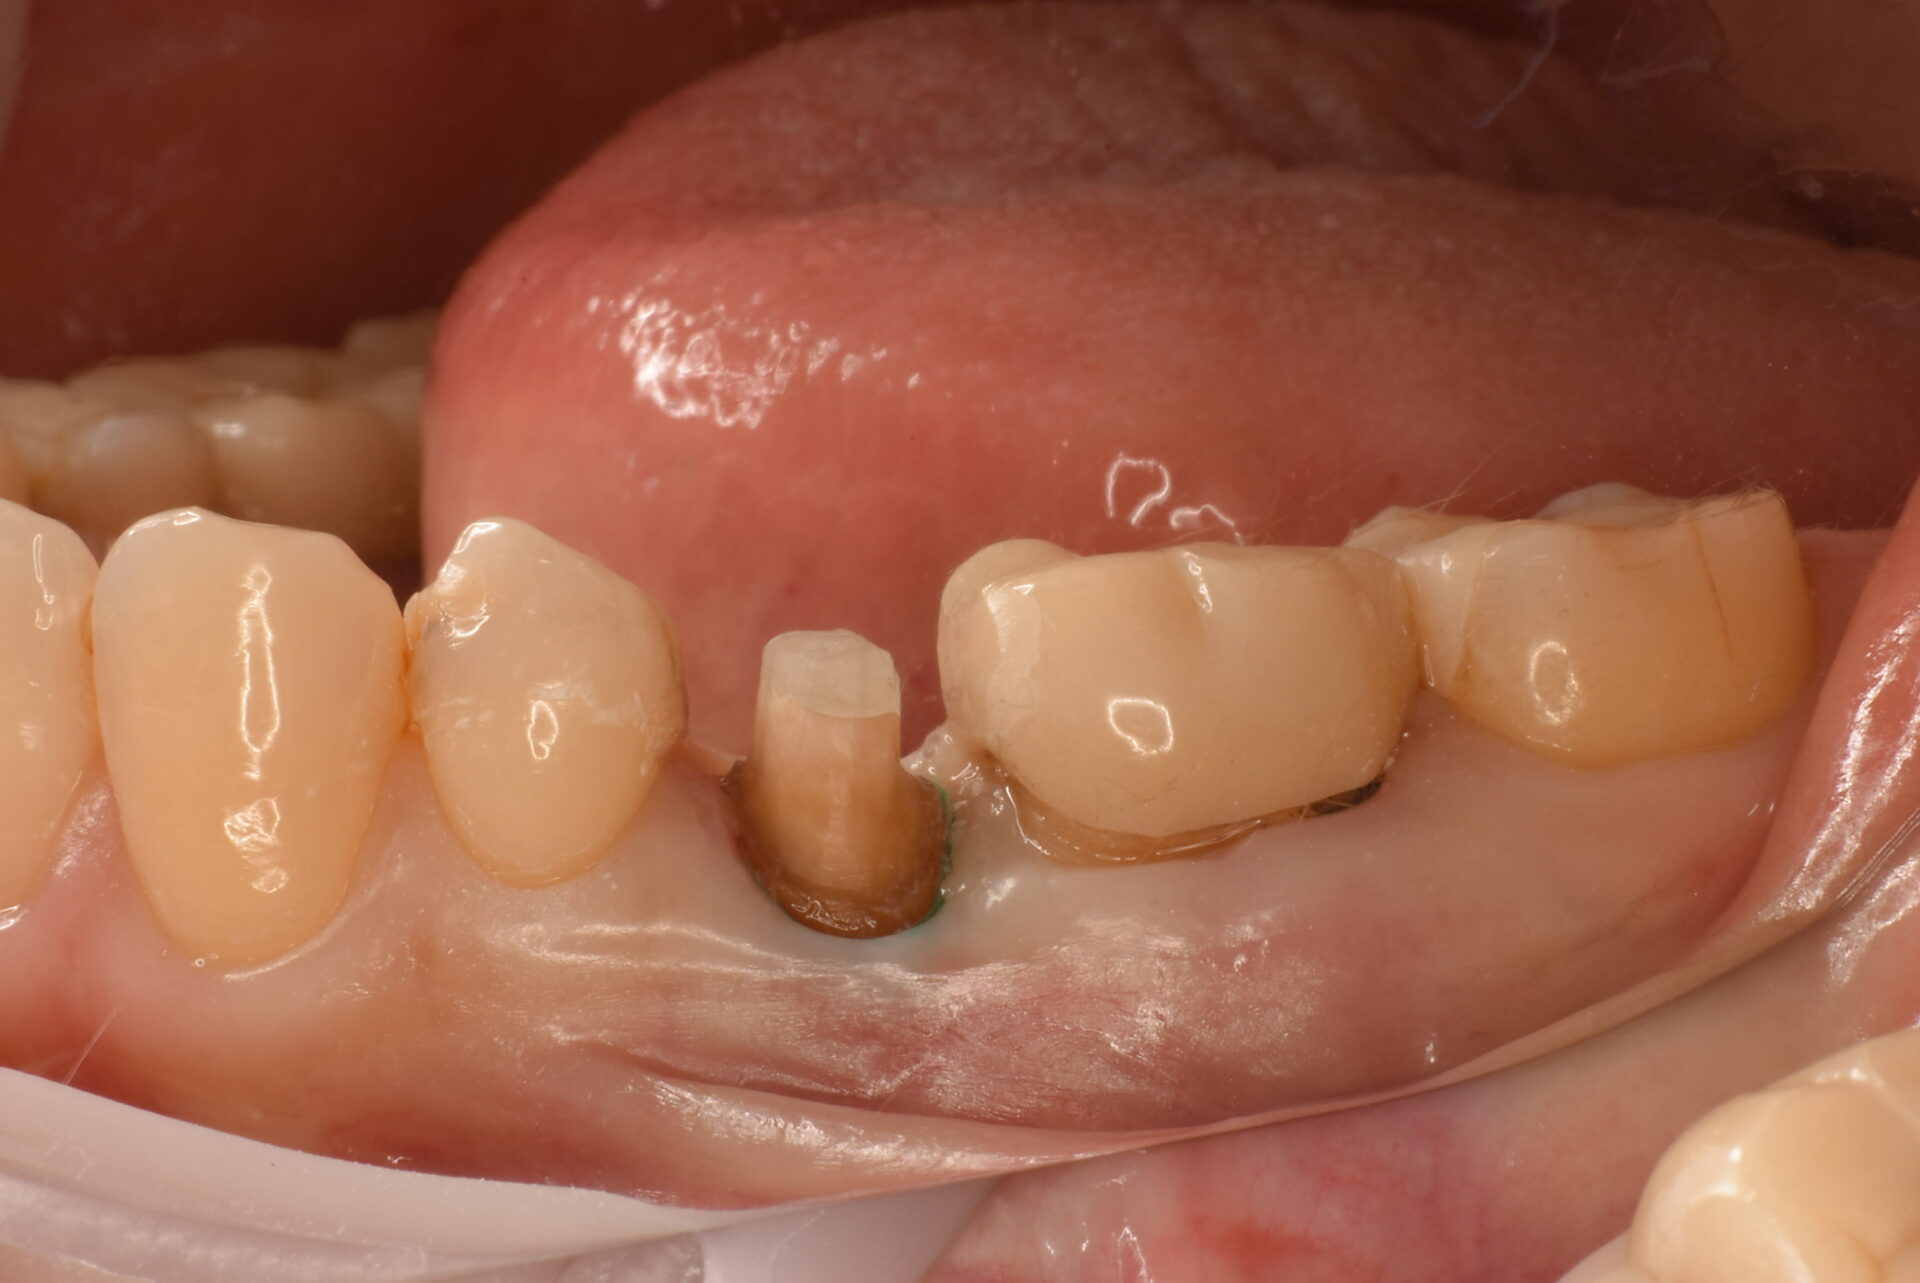

支台歯形成